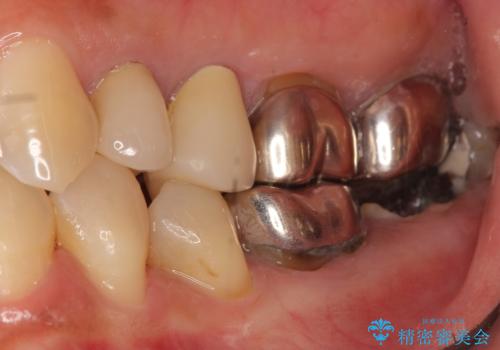

左下の奥歯(左下7)は破折しており保存不可能な状態でした。

ご希望により、隣の親知らず(左下8)を移植しました。

移植後、生着を待って根管治療及び補綴修復を行いました。

※術前にレントゲン・CTを撮影し、抜去する歯と親知らずの根の長さ・幅径・形態を確認し、移植の可否を判断してから手術を行っております。